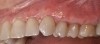

(25.) Preoperative view.

Figure 25